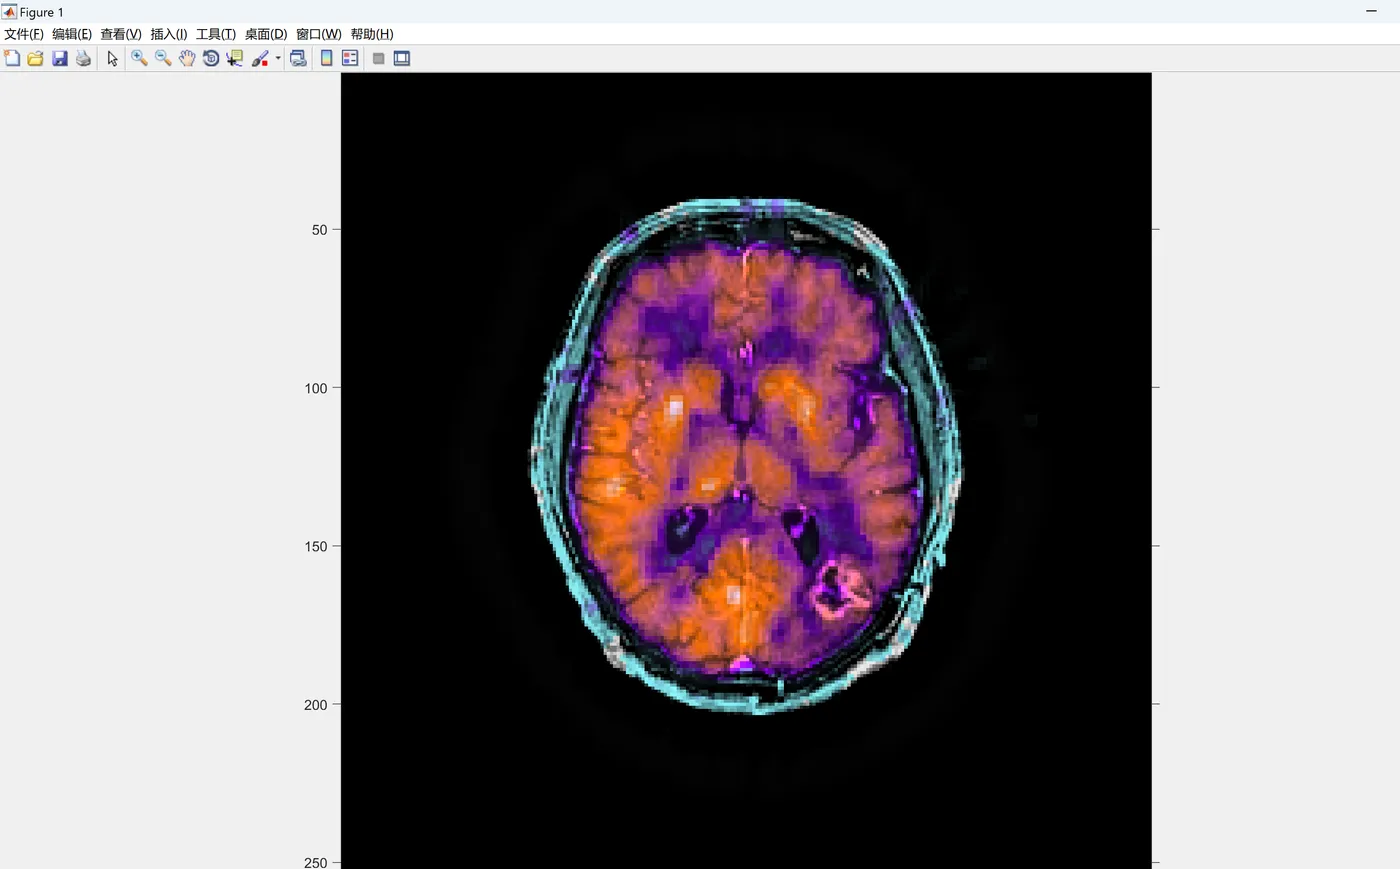

在基于图像的医学决策中,对患者的某个器官进行了不同模态的医学图像捕获。每个图像将代表一种模态,将以不同方式呈现检查的器官,导致对给定现象(如中风)的不同观察。对每种模态的准确分析有助于检测出更合适的医疗决策。多模医学成像是一个研究领域,涉及开发能够实现不同模态获取的图像信息融合的强大算法。本文提出了一种新颖的多模医学图像融合算法,适用于各种医学诊断问题。该算法基于边界测量的脉冲耦合神经网络融合策略和能量属性融合策略在非子采样切尔变换域中的应用。我们的算法在包含多种疾病模态的数据集中得到验证,包括胶质瘤、阿尔茨海默症和转移性支气管原发性肿瘤,其中包含100多对图像。定性和定量评估验证了所提出的算法优于大多数当前算法,为医学诊断提供了重要的思路。

多模医学成像是科学界近年来备受关注的研究领域,特别是由于其在医学诊断、计算机视觉和物联网方面的重要性。定义为同时生成属于不同医学成像技术的信号,在这一研究领域中最大的挑战之一是如何以有效和最佳的方式结合(或融合)多模医学成像传感器,如正电子发射断层扫描(PET)、单光子发射计算机断层扫描(SPECT)和磁共振成像(MRI)。这种图像融合过程涵盖了许多技术和研究领域,从图像处理技术、计算机视觉到模式识别,旨在促进更准确的医学诊断和更有效的医学决策。

在肿瘤诊疗领域,单一模态医学图像的局限性日益凸显。例如,CT虽能清晰显示骨骼结构,但对软组织病变的分辨率不足;MRI擅长软组织成像,却对钙化组织检测乏力;PET通过代谢活性评估肿瘤,但空间分辨率低。据统计,约70%的胸骨肿瘤病例在确诊时已处于中晚期,这与传统影像学方法的诊断效率直接相关。多模态医学图像融合技术的出现,为解决这一难题提供了关键路径——通过整合CT、MRI、PET、SPECT等模态的互补信息,可显著提升肿瘤定位、分期及良恶性判断的准确性。